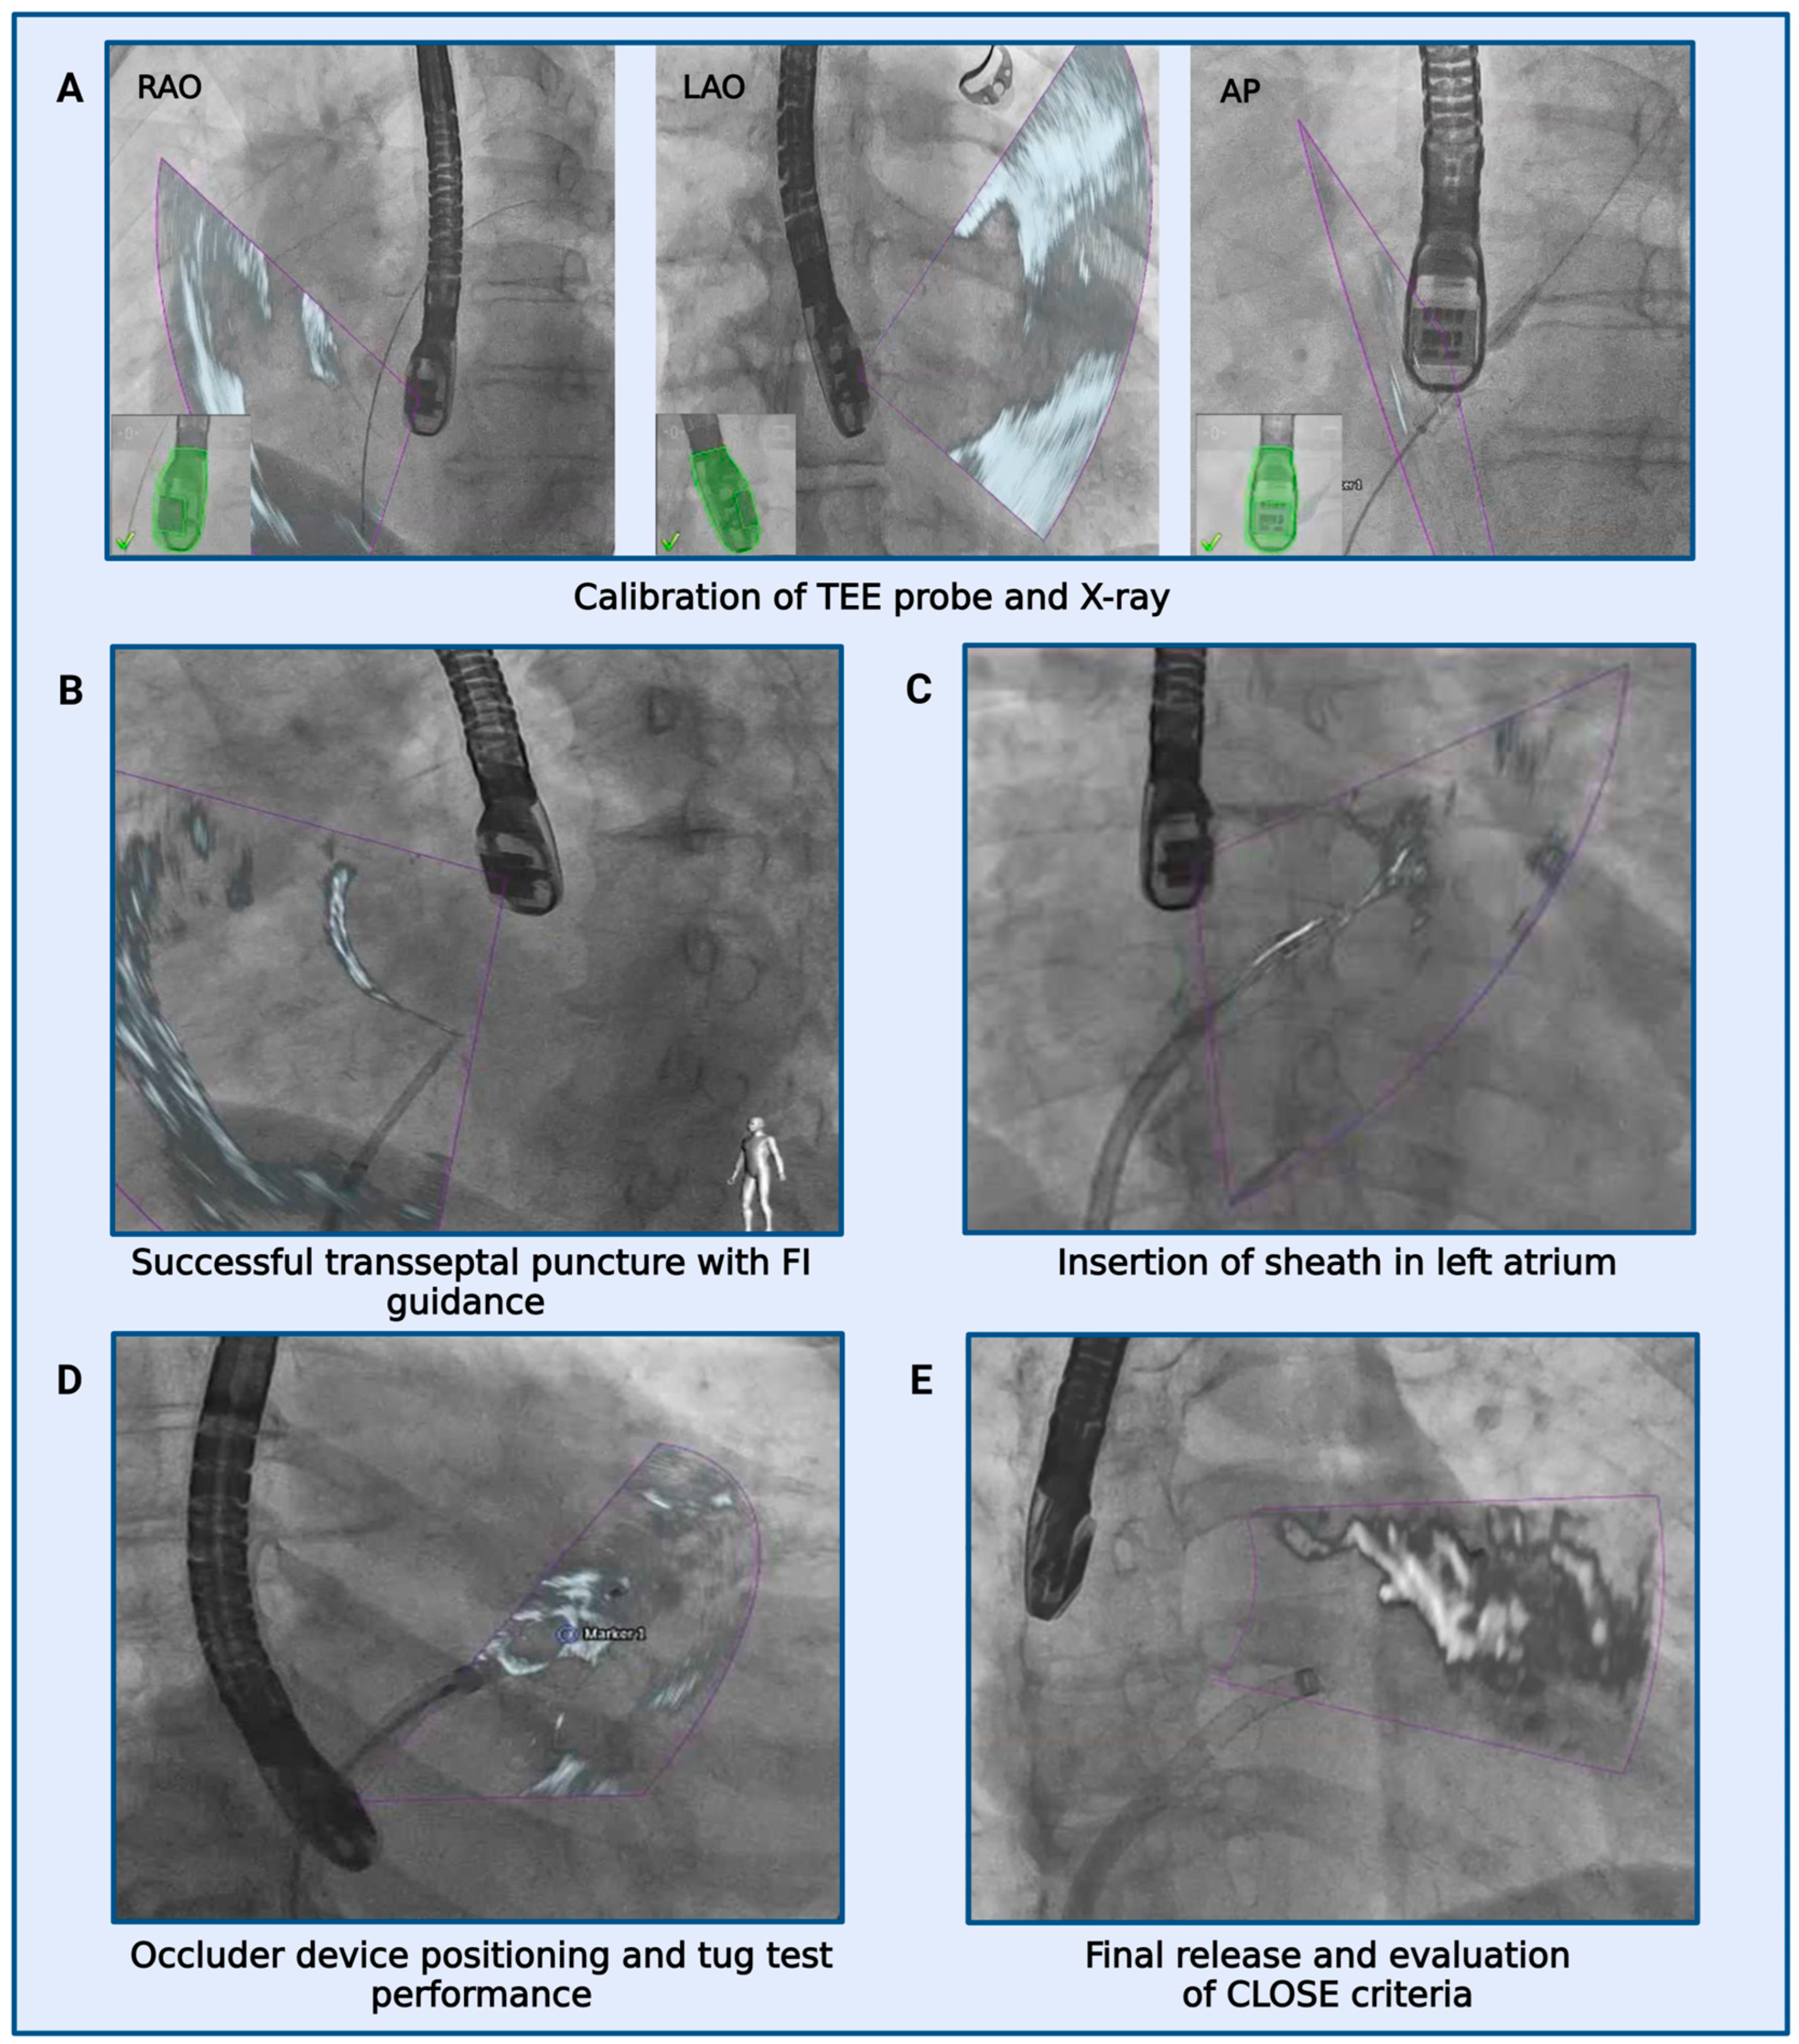

2.3. Real-Time Echocardiography-Fluoroscopy Fusion (FI) Imaging during LAAC